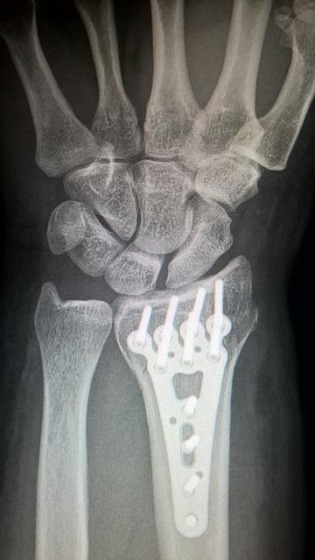

原因③尺骨茎状突起骨折

手首のレントゲン写真

ChristophMeinersmann

尺骨茎状突起は、TFCCが付着した部分の骨をいいますが、この部位が交通事故により骨折してしまった場合も手首に痛みが出ます。尺骨茎状突起骨折は、レントゲンに写るため診断は比較的容易です。

尺骨茎状突起骨折の治療を進める中で、痛みが残るようであれば、骨折箇所の接合や、骨片を取り除きTFCCを縫合する手術を行います。